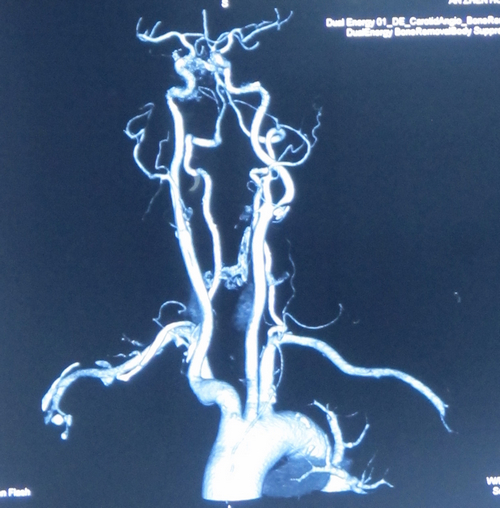

患者李某某,女,70岁,主因“头晕三年,加重伴双眼视物模糊3个月”入院。患者3年前无明显诱因出现头晕、头部不适,间断发作,半年前无明显诱因跌倒一次,未予重视。3个月前头晕加重并伴有双眼视物模糊,于脑卒中筛查门诊就诊,查颈动脉椎动脉B超:双颈动脉多发斑块,左侧颈内动脉中度狭窄。进一步查颈动脉CTA示:左侧颈内动脉开口处重度狭窄。收入院拟行CEA治疗。

张勤奕教授认为,患者2年前冠脉CTA检查未见冠状动脉重度狭窄,患者自述无心绞痛症状,考虑冠脉情况暂不予特殊处理。患者有TIA发作症状,可行头MRI检查。双侧颈动脉狭窄,以左侧为重,符合CEA手术指征,首选处理左侧颈动脉病变。